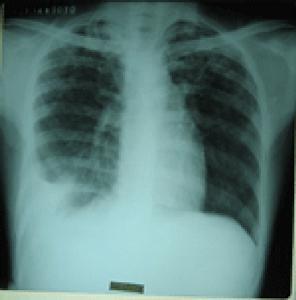

结核性胸膜炎是临床上常见的肺外结核病,是结核分枝杆菌及其代谢产物进入处于高敏状态的胸膜腔引起的胸膜炎症。结核性胸膜炎的发病与结核分枝杆菌感染及机体的免疫状态密切相关。结核性胸膜炎属于肺结核病五大类型的V型,其虽非肺部病变,但在临床上与肺结核有密切的关系。